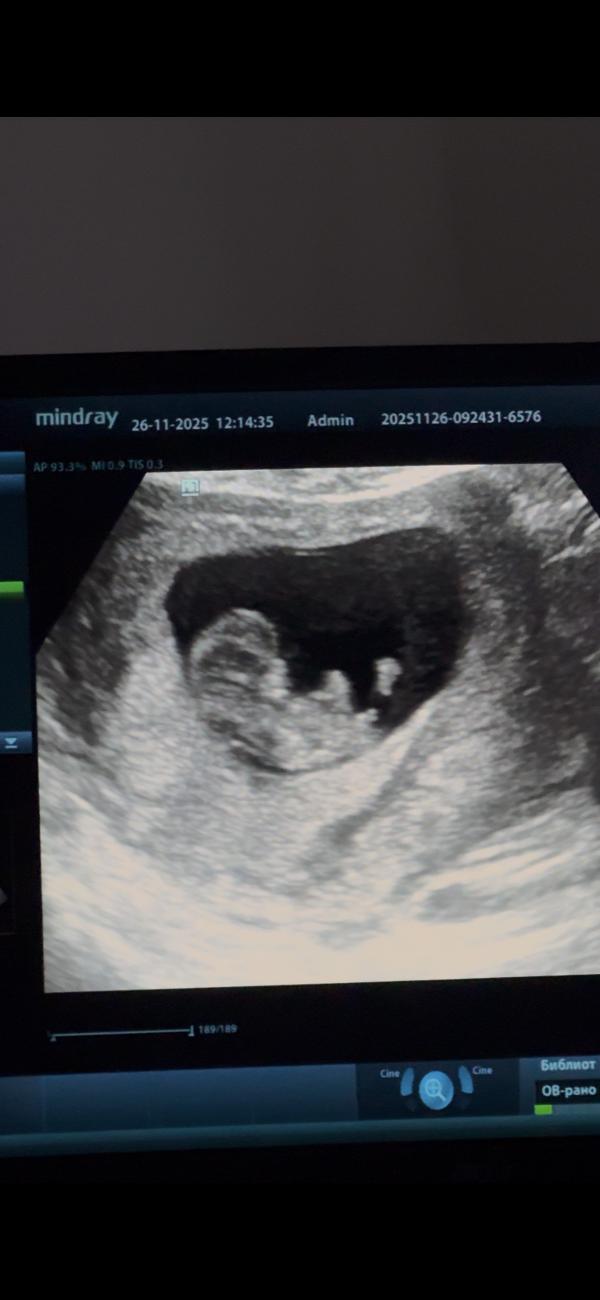

Полистайте карусель

И скажите

Мальчик это или девочка

😂

Тут не может быть ещё никаких яичек, тут тока бугорок, и то ещё рано судить, он может ещё подняться

@leyla.isl, ну в 10 недель яичек и писюна прям видно не будет по любому 😀